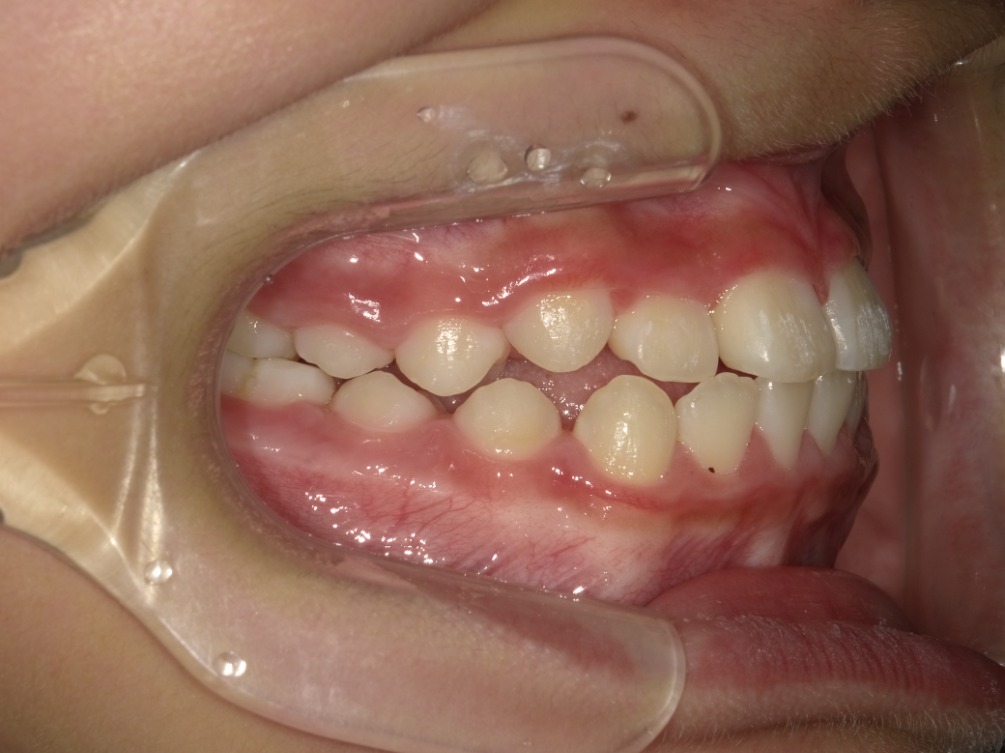

BEFORE

正面

右横

左横

| 治療内容 | インビザライン・ファースト |

| 治療詳細 | 叢生や交叉咬合を整えるために、歯の表面にアタッチメント(白い突起)をつけました。 |

| 主訴 | 歯のがたつき 一部分だけかみ合わせが反対 |